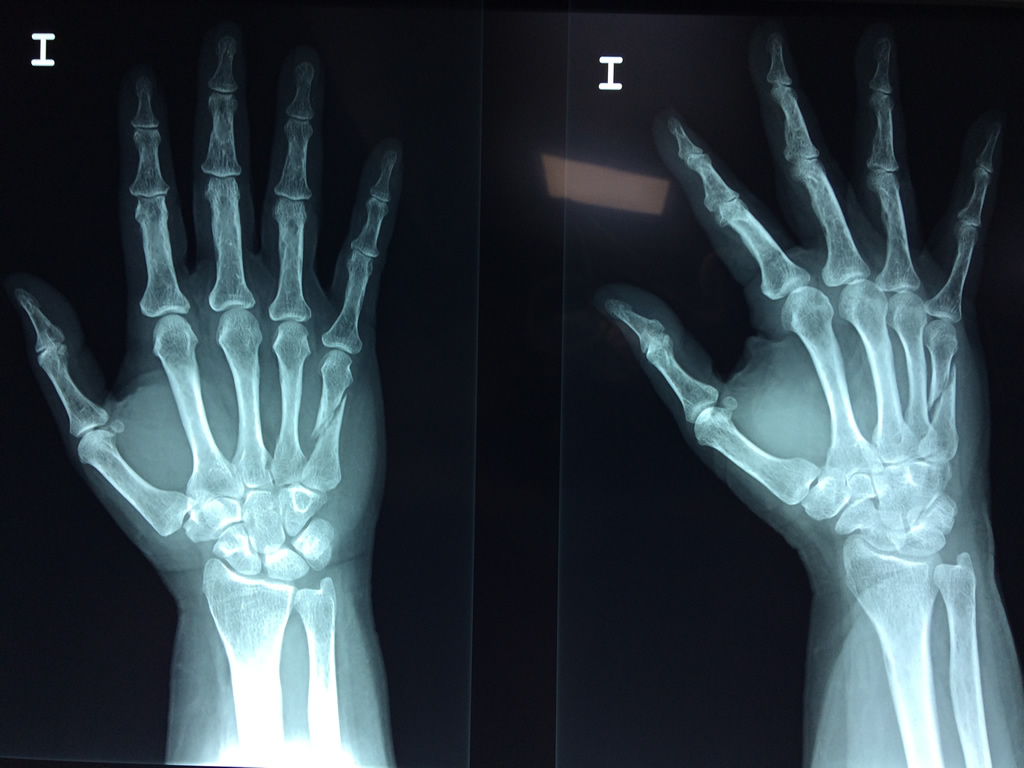

Cirugías de Húmero - Cirugías de Muñecas y Manos

Los procedimientos más comunes en cirugía de la mano son aquellos destinados a reparar traumatismos, incluyendo lesiones de tendones, nervios, vasos sanguíneos, y articulaciones; huesos fracturados; y quemaduras, cortes, y otros daños de la piel.